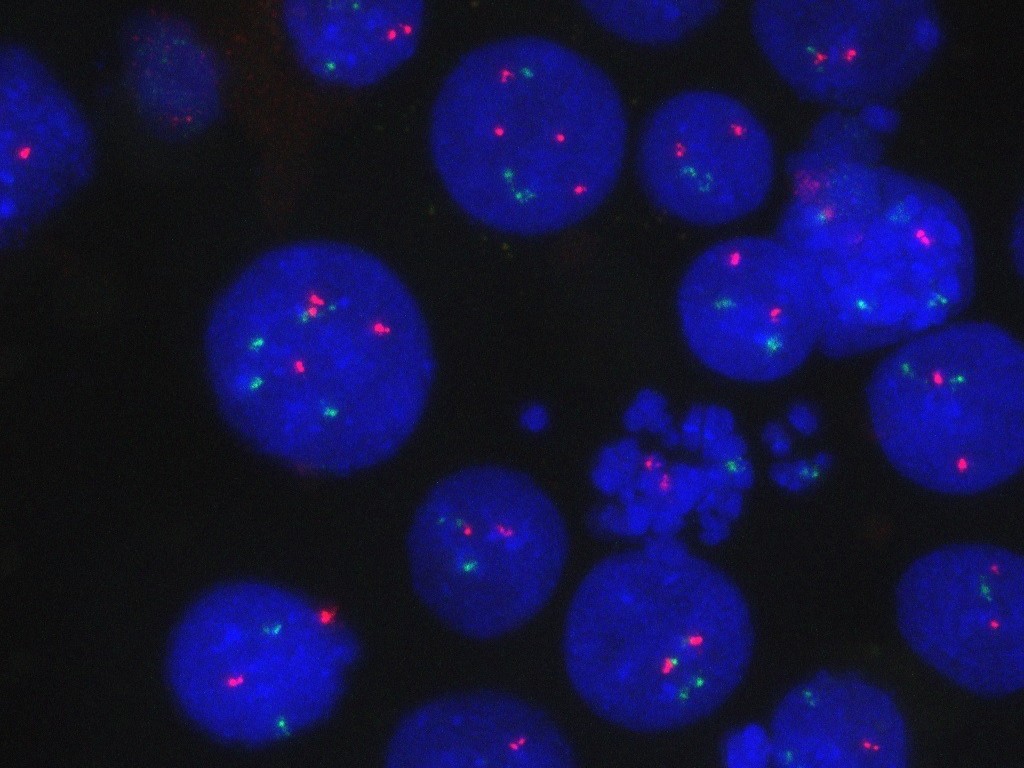

وكشفت الدراسات اللاحقة أن السيستين يُطلق سلسلة من الأحداث تؤدي إلى تنشيط مجموعة من الخلايا المناعية تُعرف بخلايا T من نوع CD8. فعندما تمتص خلايا بطانة الأمعاء السيستين من الطعام المهضوم، تحوّله إلى مركب مساعد يُعرف بـ CoA، يُفرز في بطانة الأمعاء المخاطية. وهناك، تمتص خلايا CD8 هذا المركب، مما يحفزها على التكاثر وإنتاج السيتوكين IL-22.

ويُعد IL-22 عنصراً مهماً في تنظيم تجدد الخلايا الجذعية المعوية، لكن لم يكن معروفاً سابقاً أن خلايا CD8 يمكنها إنتاجه لتعزيز هذه العملية. وبمجرد تنشيطها، تصبح خلايا T المنتجة لـ IL-22 جاهزة لمواجهة أي إصابة قد تحدث في بطانة الأمعاء.